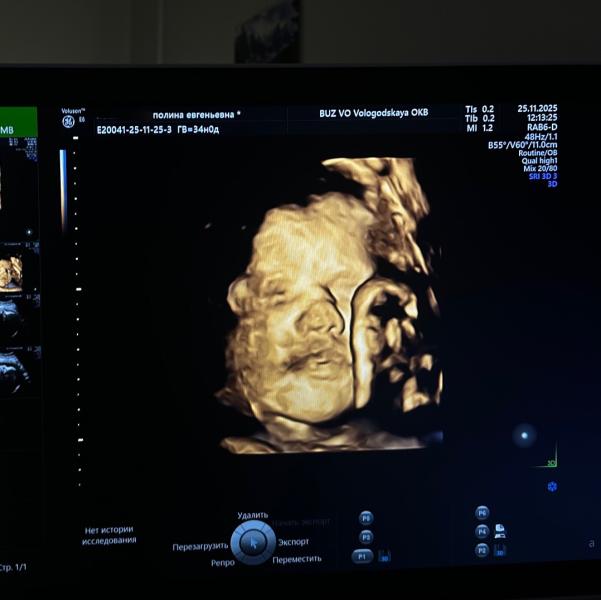

post image 1

Наша щекастая мадама🩶 34 недельки ровно.

Сегодня с нас сняли диагноз «маловесный плод»! 🎉

2094гр